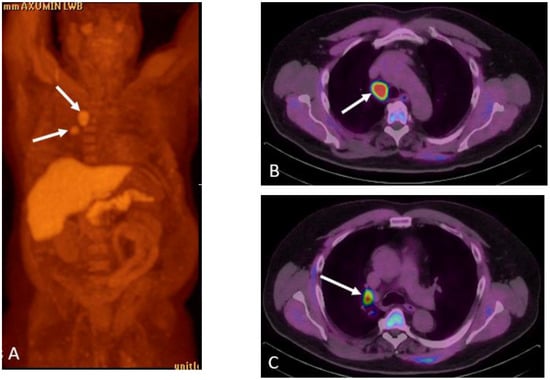

Detection of Loco-Regional Disease and Distant Metastases